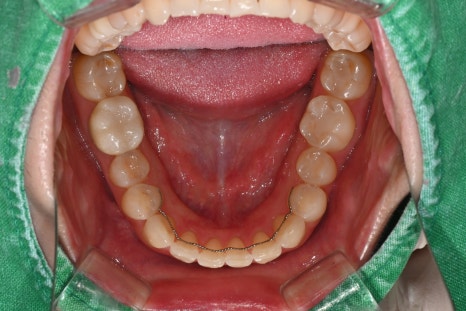

Comparison before and after treatment

<BEFORE>

A female patient in her 30s who recently visited us also

was not satisfied with the color and shape of her existing front-tooth restoration

and wanted a consultation for OBZERO Laminate,

with treatment that was as close to no-prep as possible.

At the first visit

The patient’s existing crown had become discolored,

and the border with the gums was not natural,

so she was always conscious of it in daily conversations

and when taking photos.

At the first visit, a panoramic image and oral photos were taken

to check the overall dental condition,

and because the color, translucency, and symmetry of the front tooth line

had a major impact on the overall impression,

we determined that a design combining laminate and anterior crowns

would be the most suitable.